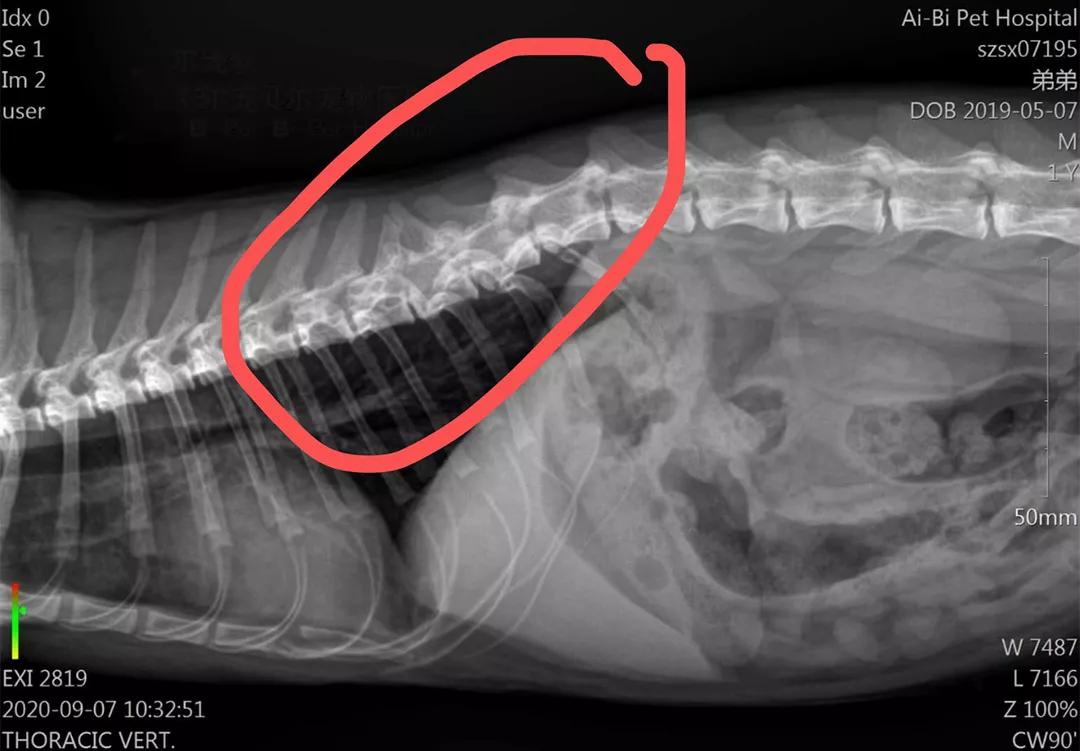

弟弟的病情十分突然,短短三天便无法走路,让人猝不及防。弟弟的主人心急如焚,在网上了解到曹浪峰宠物医院的针灸疗法,立即将弟弟转诊过来。经过X光片诊断,弟弟的腰椎先天性错位,导致双后腿急性瘫痪。